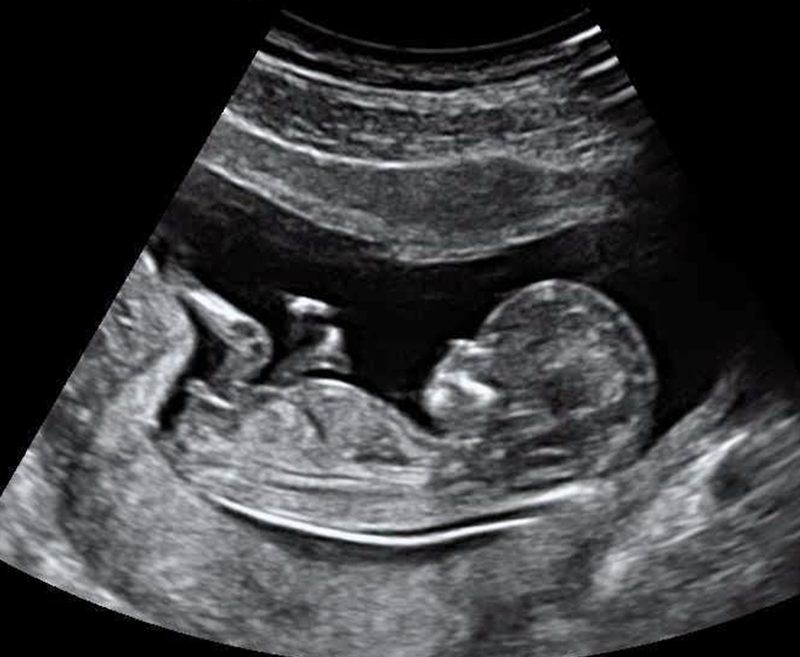

Kết quả siêu âm độ mờ da gáy đạt độ chính xác cao nhất khi được thực hiện từ tuần thứ 11 đến tuần thứ 13 của thai kỳ. Đây là khoảng thời gian lý tưởng vì các lý do sau:

Siêu âm độ mờ da gáy là một quy trình quan trọng trong quá trình khám thai, đặc biệt khi thai phụ có tử cung nghiêng về sau hoặc thừa cân, béo phì. Để đạt được kết quả chính xác nhất, bác sĩ thường tiến hành siêu âm đầu dò.

Trước khi tiến hành siêu âm, bác sĩ sẽ bôi một lớp gel lên bụng của thai phụ để giảm ma sát và tạo điều kiện cho đầu dò di chuyển mượt mà trên da. Sau đó, bác sĩ sử dụng đầu dò để quét lên da bụng của thai phụ.

Đầu tiên, bác sĩ sẽ đo chiều dài của thai nhi từ đỉnh đầu đến cuối xương sống để xác định tuổi thai nhi. Tiếp theo, họ sẽ đo độ mờ da gáy bằng cách đo khoảng cách từ da đến phần dịch tích tụ sau gáy.